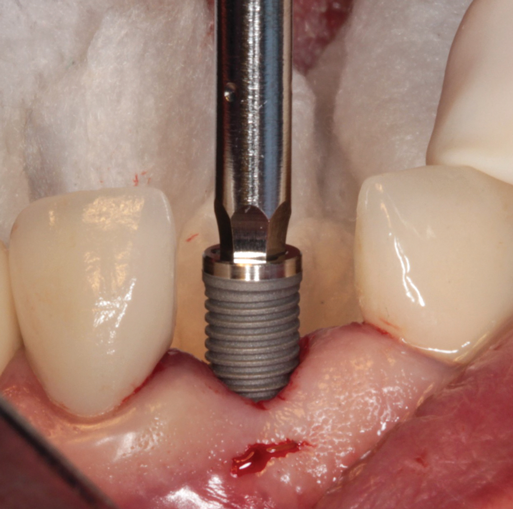

(12.) Placement of an appropriately sized implant into the osteotomy.

Figure 12

(13.) The appropriateness of the apical depth of the implant head was confirmed.

Figure 13